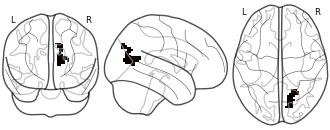

"description": "Multi-modal analysis in BPD. Brain regions exhibiting smaller gray matter and enhanced activation during emotion processing in BPD compared to healthy controls. Note: Results were thresholded at p<.0025. Note2: Results were updated (see Erratum for this publication).",